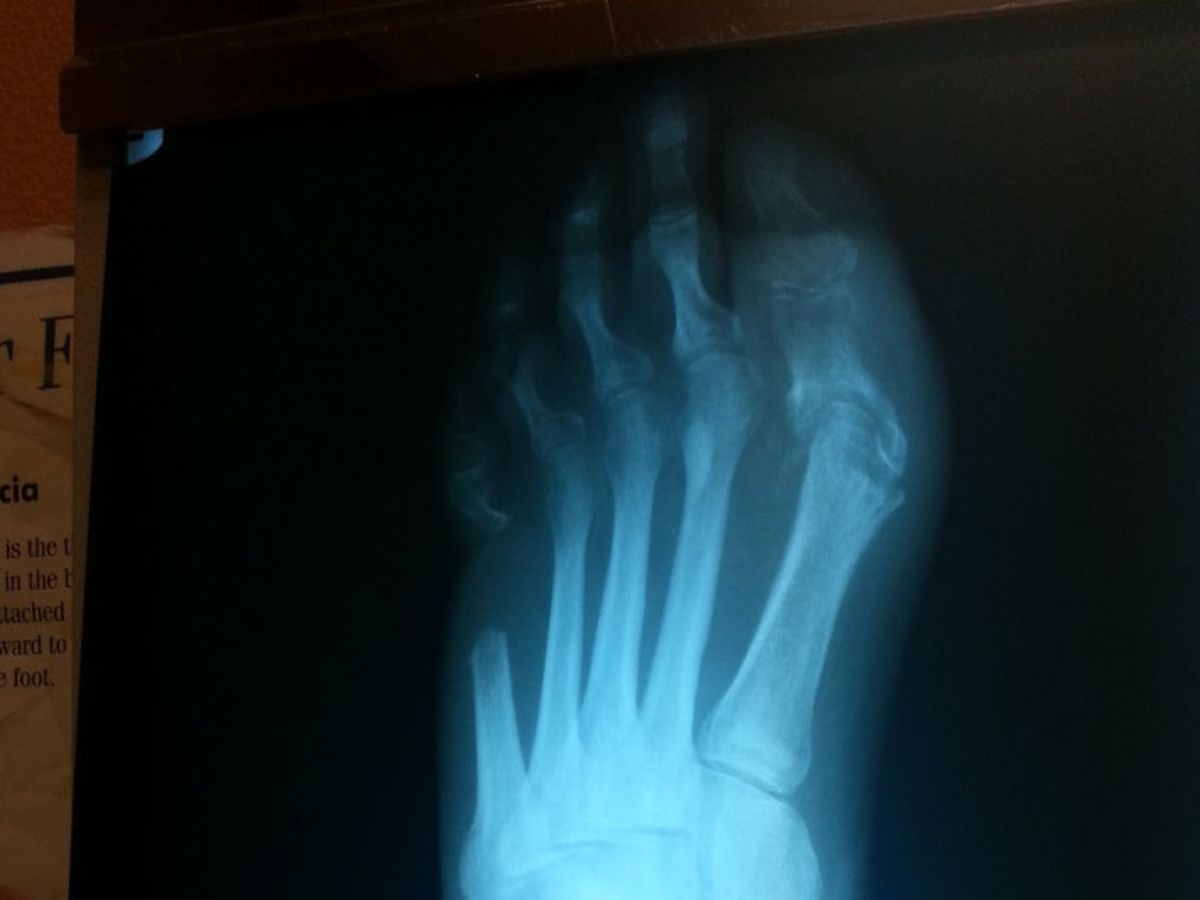

through most of 2016 I have been getting treatment for a bone infection in my left foot. Following the treatment plan of my podiatrist, I endured having a PICC line implanted in my arm, through to my heart, and went for IV antibiotic treatment 3 hours a day, 7 days a week, for 8 weeks. Blood work was done during the treatment as well as after, and all the reports said there was no sign of infection. But that was not true - the massive amounts of antibiotics only put the bone infection into "remission" of sorts. When it recurred, I was referred to a surgeon that scheduled immediate surgery to save my foot and remove an approximate 2" piece of the 5th metatarsal including the deteriorated/infected bone, plus additional bone to make sure the infected bone removal was complete.